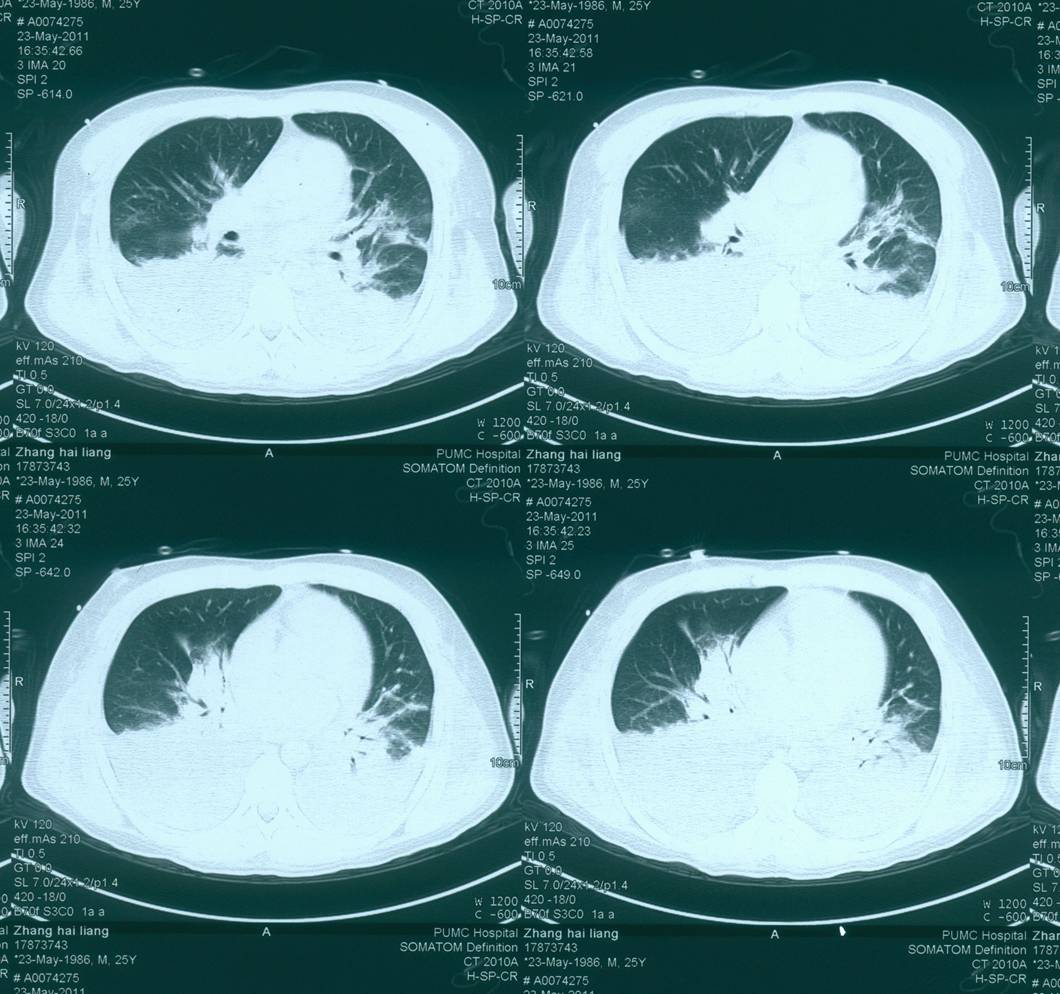

◆胸部CT:双肺实变,双侧胸腔积液伴双肺膨胀不全,心衰可能

现病史-超声心动

——复查胸部CT是双肺内新发斑片影

2天后复查CT:双肺渗出病灶明显吸收